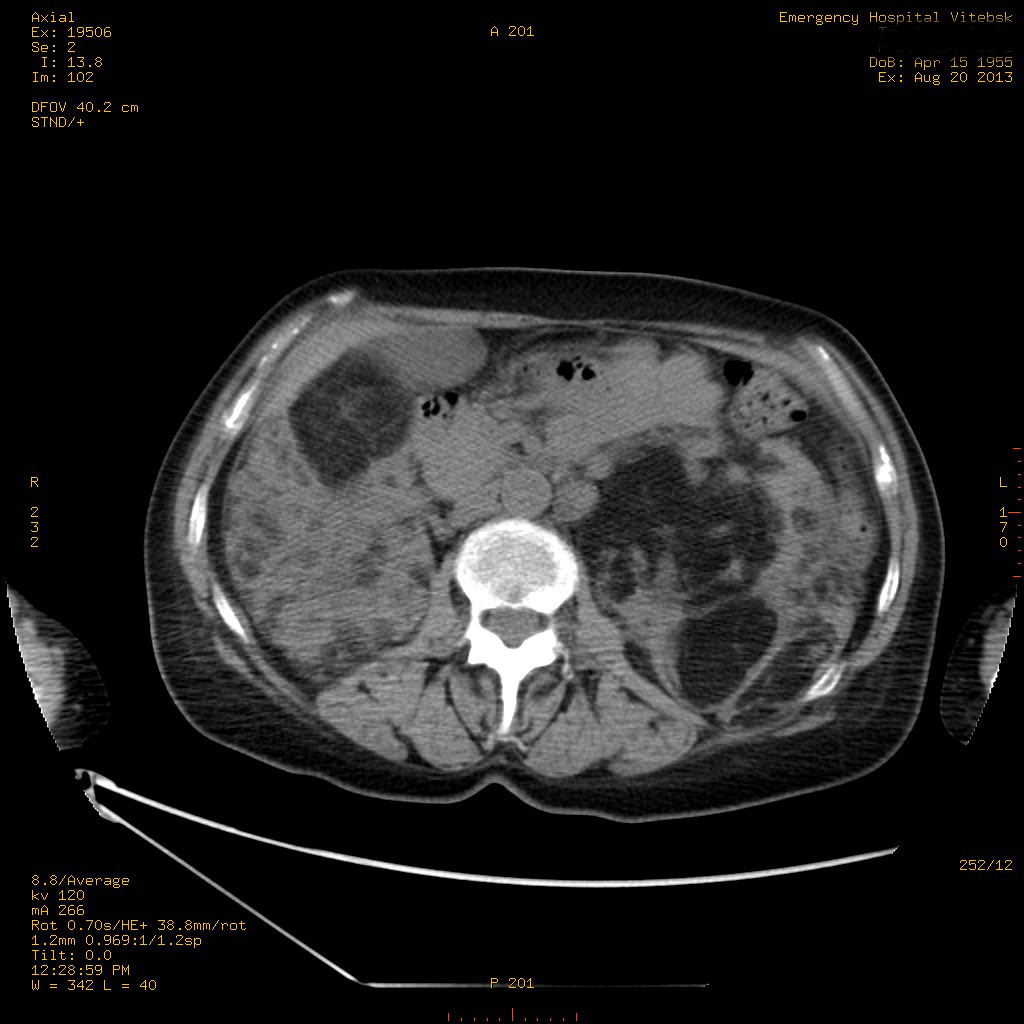

УЗИ почек - туберозный склероз

Пожилая женщина с нормальными мочевиной и креатинином.

Ангиомиолипоматоз почек , думаю компонент туберозного склероза.

Да, туберозный склероз.

Случай консультирован на кафедре радиологии Католического университета г.Лёвен (Бельгия) - зав каф. профессор Р.Оуен.